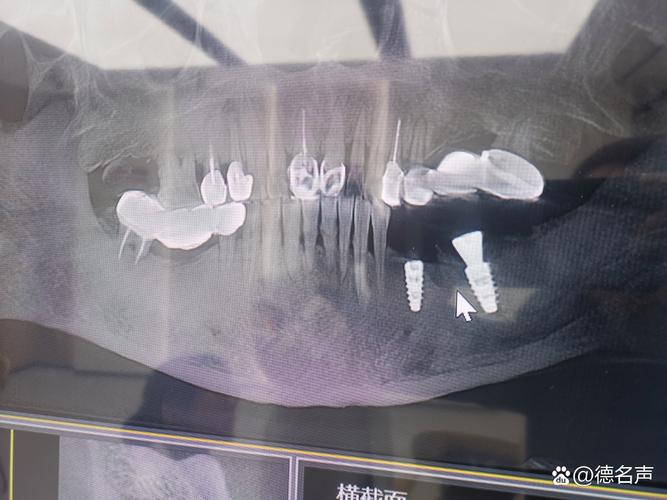

- 靠近口腔的检查(如头颈部MRI,尤其是颞下颌关节、鼻咽、口腔颌面部等): 种植体及其上部结构(尤其是金属烤瓷牙冠)产生的伪影可能非常显著,会严重干扰目标区域的图像,导致诊断困难或无法进行。

- 种植牙数量和位置: 单个种植牙的影响通常有限,多个种植牙或种植牙位于扫描野中心时,伪影范围会更大。